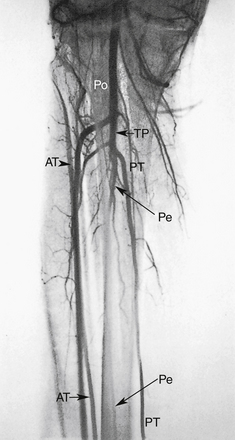

РИСУНОК 13-12. Передняя большеберцовая артерия (ПП) идет переднелатерально от своего основания и проходит через межкостную перепонку. Затем он проходит вдоль передне-латеральной стороны голени к стопе. Большеберцово-перонеальный ствол (ТП) имеет переменную длину и обычно раздваивается на малоберцовую (Пе) и заднюю большеберцовую (ПТ) артерии. Малоберцовая артерия, также показанная на рис. 13-11 , Б , проходит вниз по ноге чуть выше лодыжки. Задняя большеберцовая артерия продолжается заднемедиальным путем до стопы. Po, подколенная артерия.

РИСУНОК 13-18. Окклюзию дистальной подколенной (Po) артерии можно обойти следующим образом: (1) икроножная (Su) и малая мышечная ветви → к возвратной передней большеберцовой артерии (rAT), которая кровоснабжает переднюю большеберцовую артерию (AT); (2) икроножная (Su) и малые мышечные ветви → к задней большеберцовой артерии (PT).